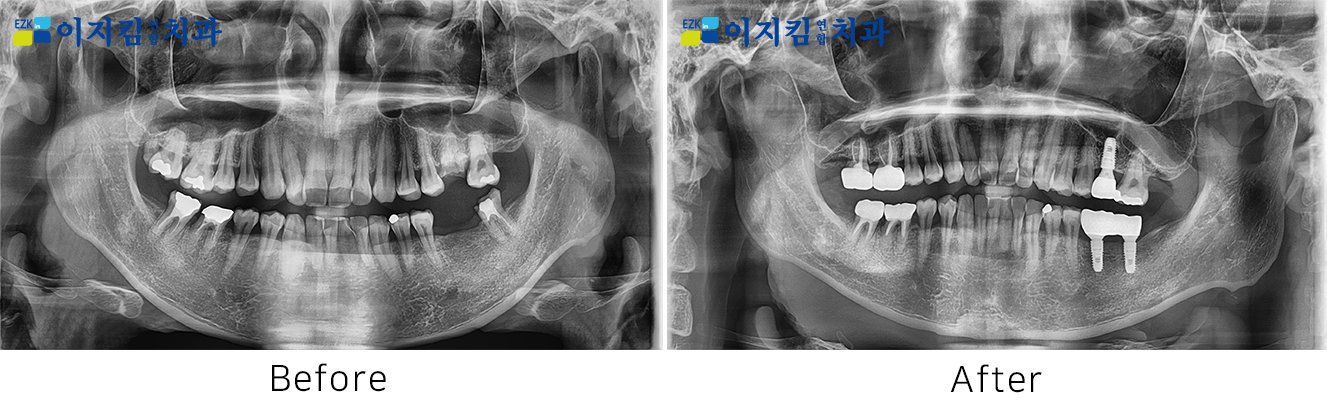

ÀÓÇöõÆ® Àü ¡¤ ÈÄ »çÁø

[

Á¶È¸¼ö : 3173

]